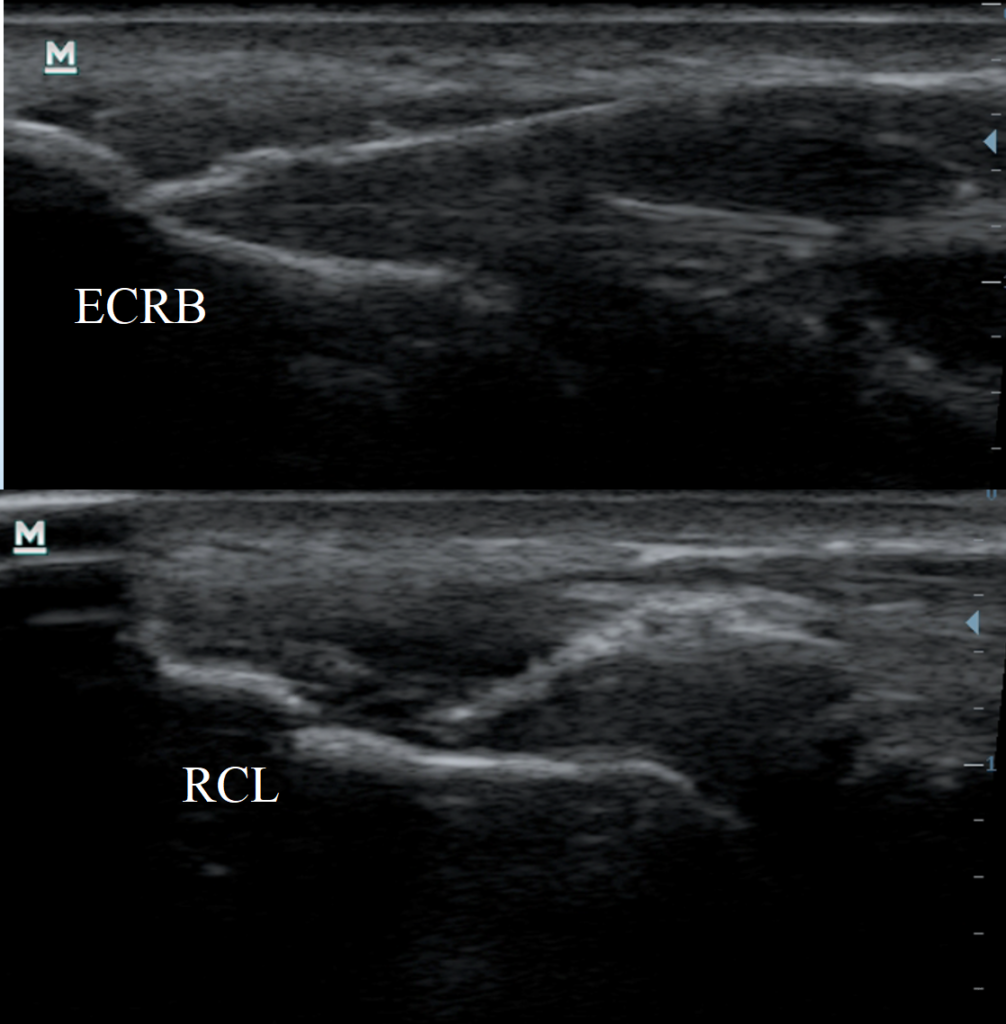

Procedura lecznicza polega na wprowadzeniu igły do akupunktury w obszary zmienione obrazowo w ECRB i RCL, przepuszczeniu przez nie niskonapięciowego mikroprądu galwanicznego. Igła wprowadzana jest pod kątem 30° i 45° w stosunku do osi długiej ścięgna (zdj. 4).